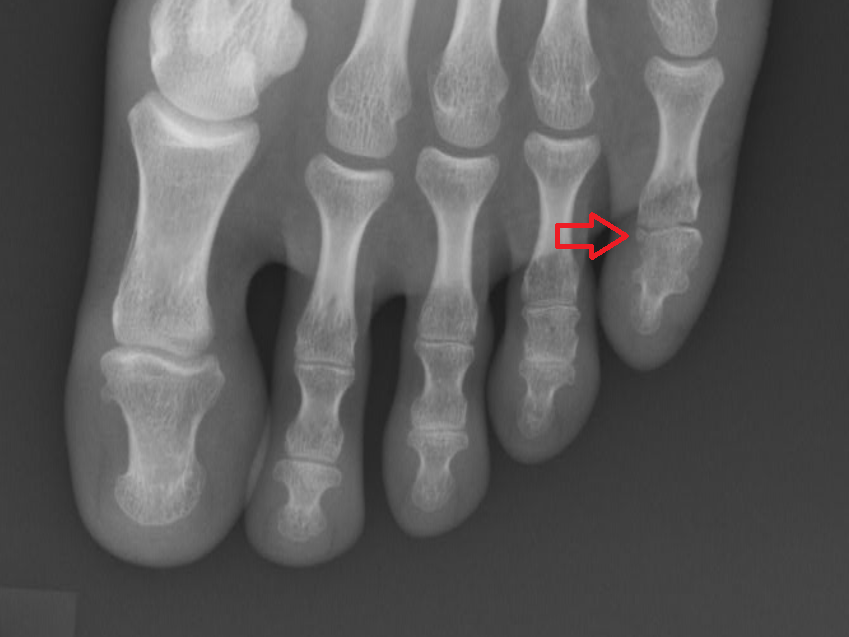

진단 방법과 X-ray 검사

의사는 통증 부위와 발가락 변형을 육안으로 확인한 뒤, X-ray로 골절선의 위치와 전위(뼈의 어긋남) 여부를 판별합니다. 단순 골절인지, 관절면을 침범한 복합 골절인지에 따라 치료 방향이 달라집니다. 경우에 따라 CT 촬영이 필요할 수도 있습니다. 엄지발가락처럼 체중이 집중되는 부위일수록 정확한 영상 진단이 중요합니다.